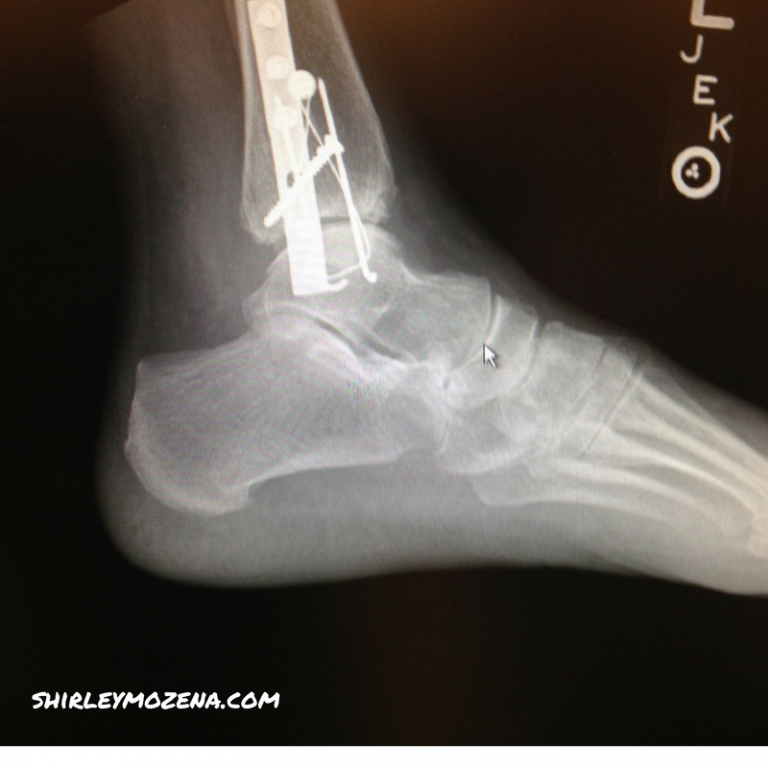

It was my first hike since the bunion surgery. We were camping in our new RV. On that Saturday evening before Mother’s Day, I ran over to our campsite to find something to share with our camping friends, when I tripped on the stairs of the RV and fell about three feet onto the ground. I felt sharp pain and again knew I’d done something serious to the left foot. Turns out I shattered my ankle and had to have surgery to repair the seven broken pieces with screws, a plate, a pin and a corkscrew.

- Repaired shattered ankle

That break was different. It was more painful. I stayed in the hospital for two nights, had to have physical therapy, and was laid up for most of the summer. A friend loaned me her knee scooter which helped, but it was still inconvenient, yet it healed nicely with the excellent medical care. The two scars on either side of the ankle are a reminder of the serious break. Yet, I wore high heels last Sunday and they felt fine.